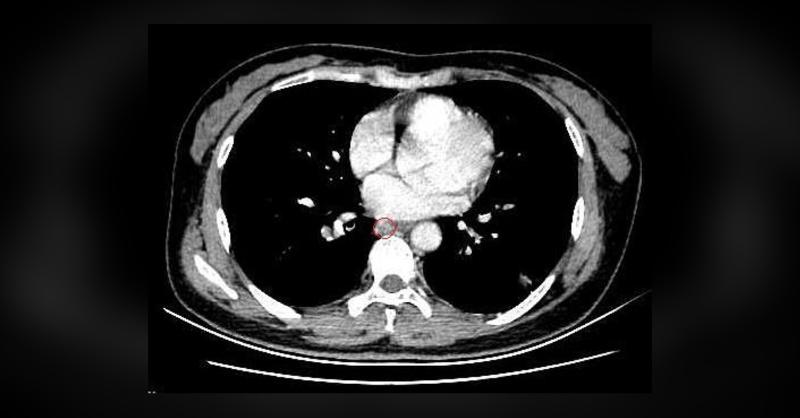

A 52-year-old woman presented following the incidental discovery of multiple right pulmonary nodules on a CT scan performed five months prior. She was asymptomatic at the time of admission. A chest CT scan demonstrated multiple ground-glass opacities located in the right superior and inferior pulmonary lobes. Additionally, a sharply marginated mass